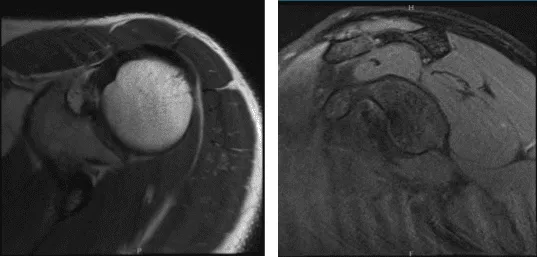

Se presentaron y discutieron radiografías del hombro izquierdo y mostraron radiografías normales del hombro izquierdo. Recomendó al paciente que se sometiera a una resonancia magnética para ver la causa del dolor. Descubrí que hay muy poca osteoartritis articular AC. No se visualiza ningún entesófito subacromial. También se notó una leve tendinosis del manguito rotador.

MRI-3T Hombro Izquierdo sin contraste